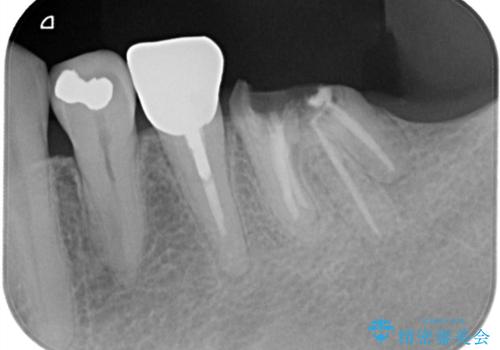

- 「奥歯の銀歯が取れた」を主訴に来院された患者さんです。

診査診断を行った結果、歯が折れた位置が深く、虫歯にもなっていたため抜歯後、インプラントで治療を行いました。

残根状態の歯を抜歯後、抜歯窩の治癒を待ちインプラントを埋入しています。